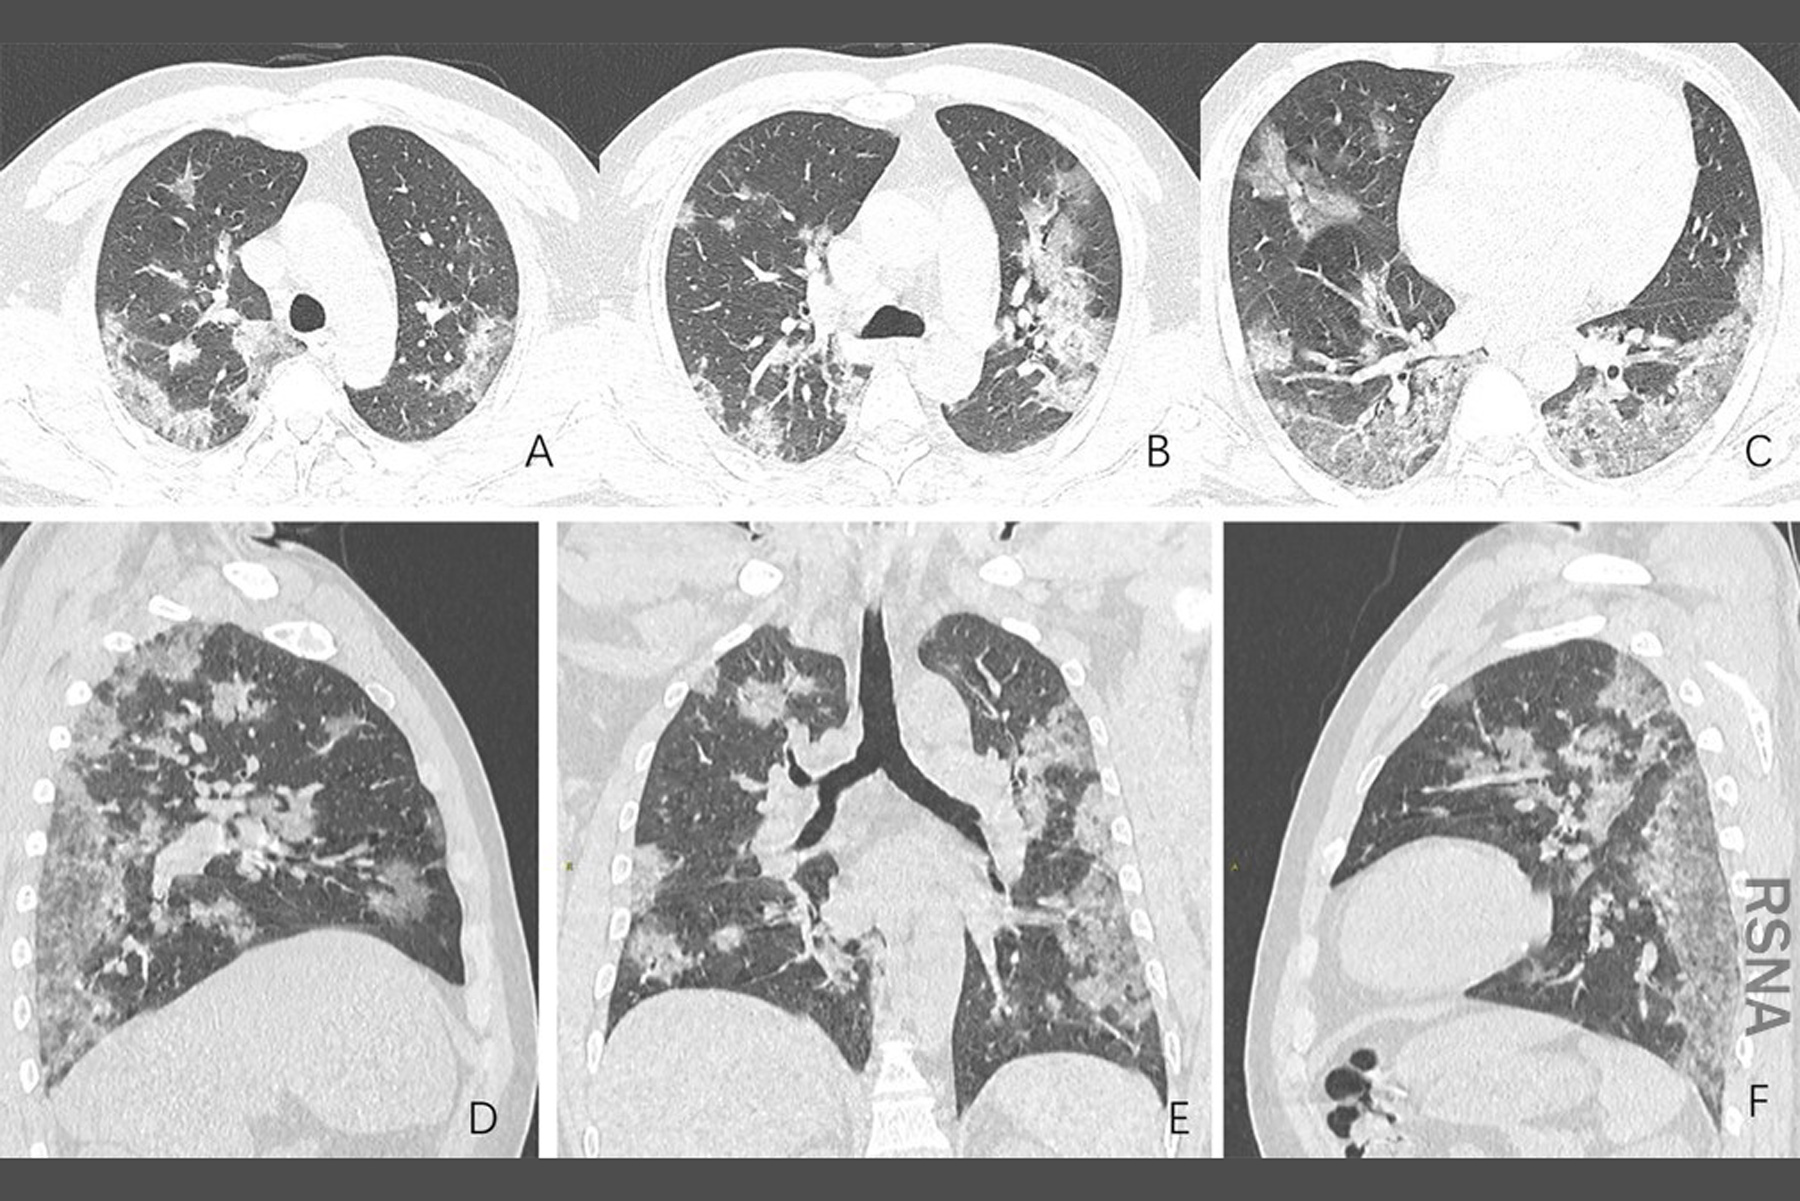

폐손상이 있게 되면 폐조직 자체는 회복이 이전처럼 당연히 될 수 없기 때문에 호흡기계 장애가 남을 수 있지만

코로나 바이러스에 걸린 사람들의 후유증은 다른 여러가지 증상이 있으며, 다른 증상들도 증상이 오래 남는다고 합니다.

정리해보면 피곤함, 숨참, 기침, 관절통, 흉통 이 남을 수 있으며 그 외에도 근육통, 심장박동의 이상, 맛과 향을 못느낌, 기억력이나 집중력장애(브레인포그), 수면장애, 탈모 등이 생길 수 있습니다.